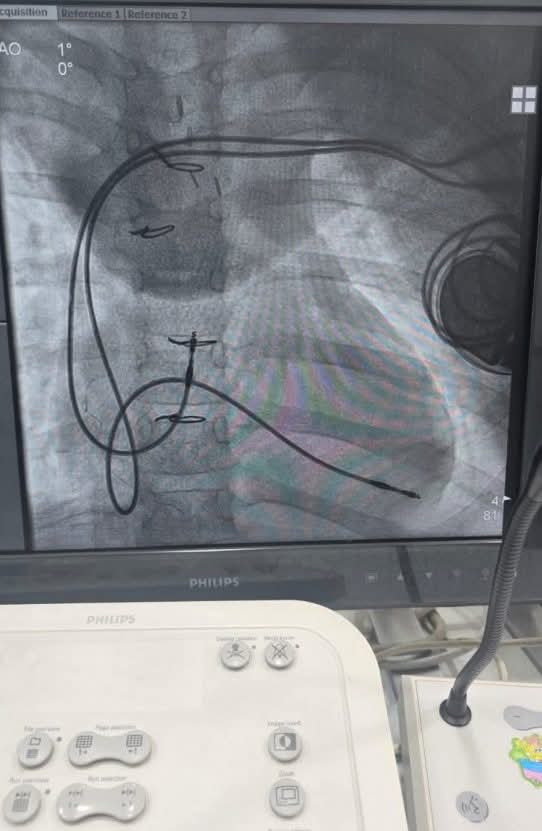

تدريسي في كلية طب المستنصرية يجري عملية قسطارية نوعية منقذة للحياة لطفلة في مركز ابن البيطار التخصصي لجراحة القلب بقلم : شريف هاشم - بغداد أجرى الأستاذ المساعد الدكتور أرشد فؤاد رضا ( التدريسي في فرع الطب الباطني في كلية الطب / الجامعة المستنصرية – إستشاري أمراض القلب والأوعية الدموية